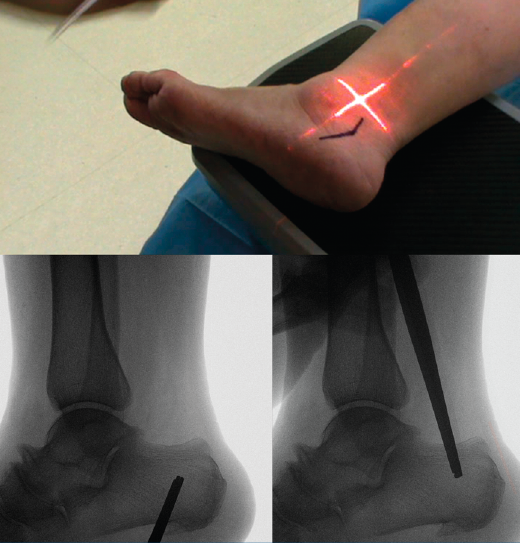

Figura 3. Se realiza bajo fluoroscopia el diseño de la osteotomía y se marca sobre la piel.

Marcamos el vértice de la V en la piel dentro de la zona de seguridad, desde donde marcamos una línea plantar paralela al borde posteroinferior de la tuberosidad y una linea dorsal paralela al borde posterosuperior de la tuberosidad (Figura 3).